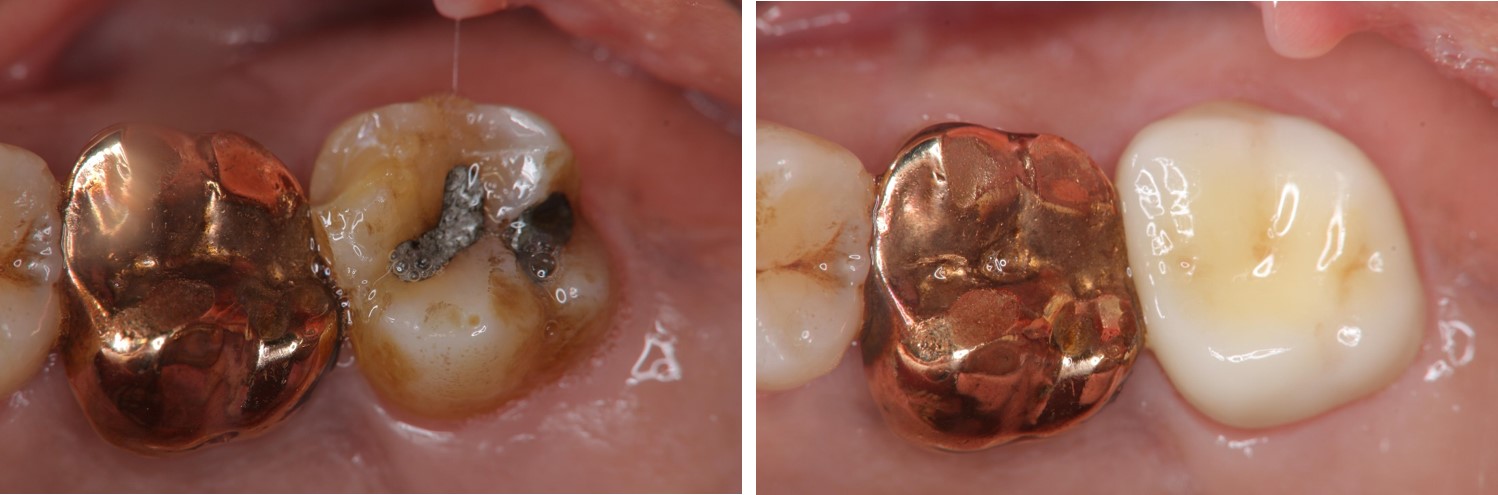

治療前,左上第二大臼齒二次蛀牙

左上第二大臼齒二次蛀牙

治療後口內照

全鋯冠密合度良好

術前、術後比較